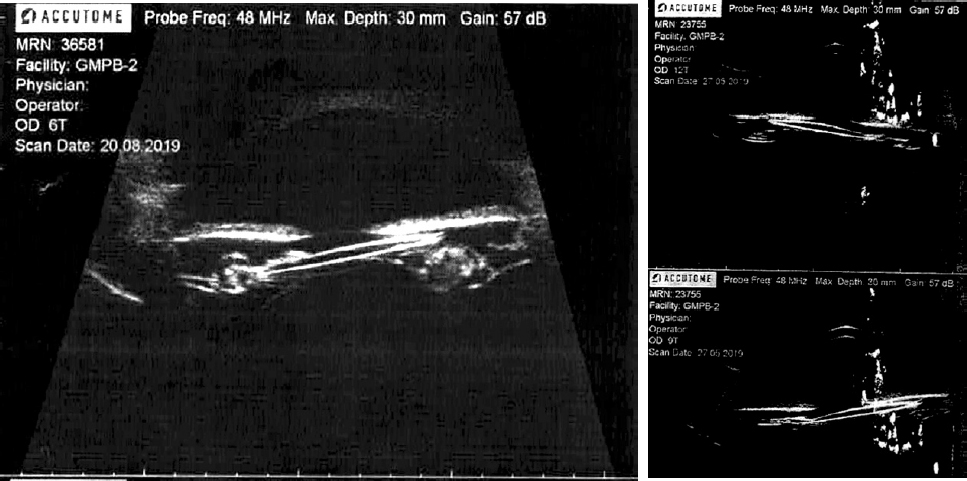

In the table 2, the results are shown of the UBM of the anterior segment performed in 37 patients of the study group. The Figure 2 demonstrates a typical position of the S-shaped IOL leading to the UGH syndrome development.

Fig. 2. Typical S-shaped single piece IOL position leading to uveitis–glaucoma–hyphema syndrome development. Tilt of optical part with haptic element displacement into the ciliary sulcus

Рис. 2. Типичное положение S-образной интраокулярной линзы, приводящее к развитию синдрома «увеит – глаукома – гифема». Наклон оптической части со смещением гаптического элемента в борозду цилиарного тела

As the second significant major risk factor for the UGH syndrome development appeared the extracapsular (mixt and sulcus) IOL fixation encountered, according to UBM data, in 54 and 19% of cases, correspondingly. A not rare cause for alternative intracapsular IOL fixation methods is the rupture of the posterior capsule, the prevalence of which (18%) in the study group, by an order of magnitude exceeded its mean prevalence in cataract surgery — 1.8% [18].

The mechanism of iris traumatization in extracapsular IOL position is obvious, as opposed to UGH syndrome development in endocapsular IOL position established in 27% of patients. The UBM data analysis allowed revealing a typical for S-shaped IOLs angulation of the haptic element leading to the slope of the artificial lens (59%) and to the subsequent migration its haptic element into the ciliary body sulcus which is conditioned by the capsular bag fibrosis and Soemmering’s ring formation (Figure 3). In some cases, an extruding of the IOL’s optic from the capsular bag occurred with preservation of it’s the position of haptic elements in the crystalline lens bag.